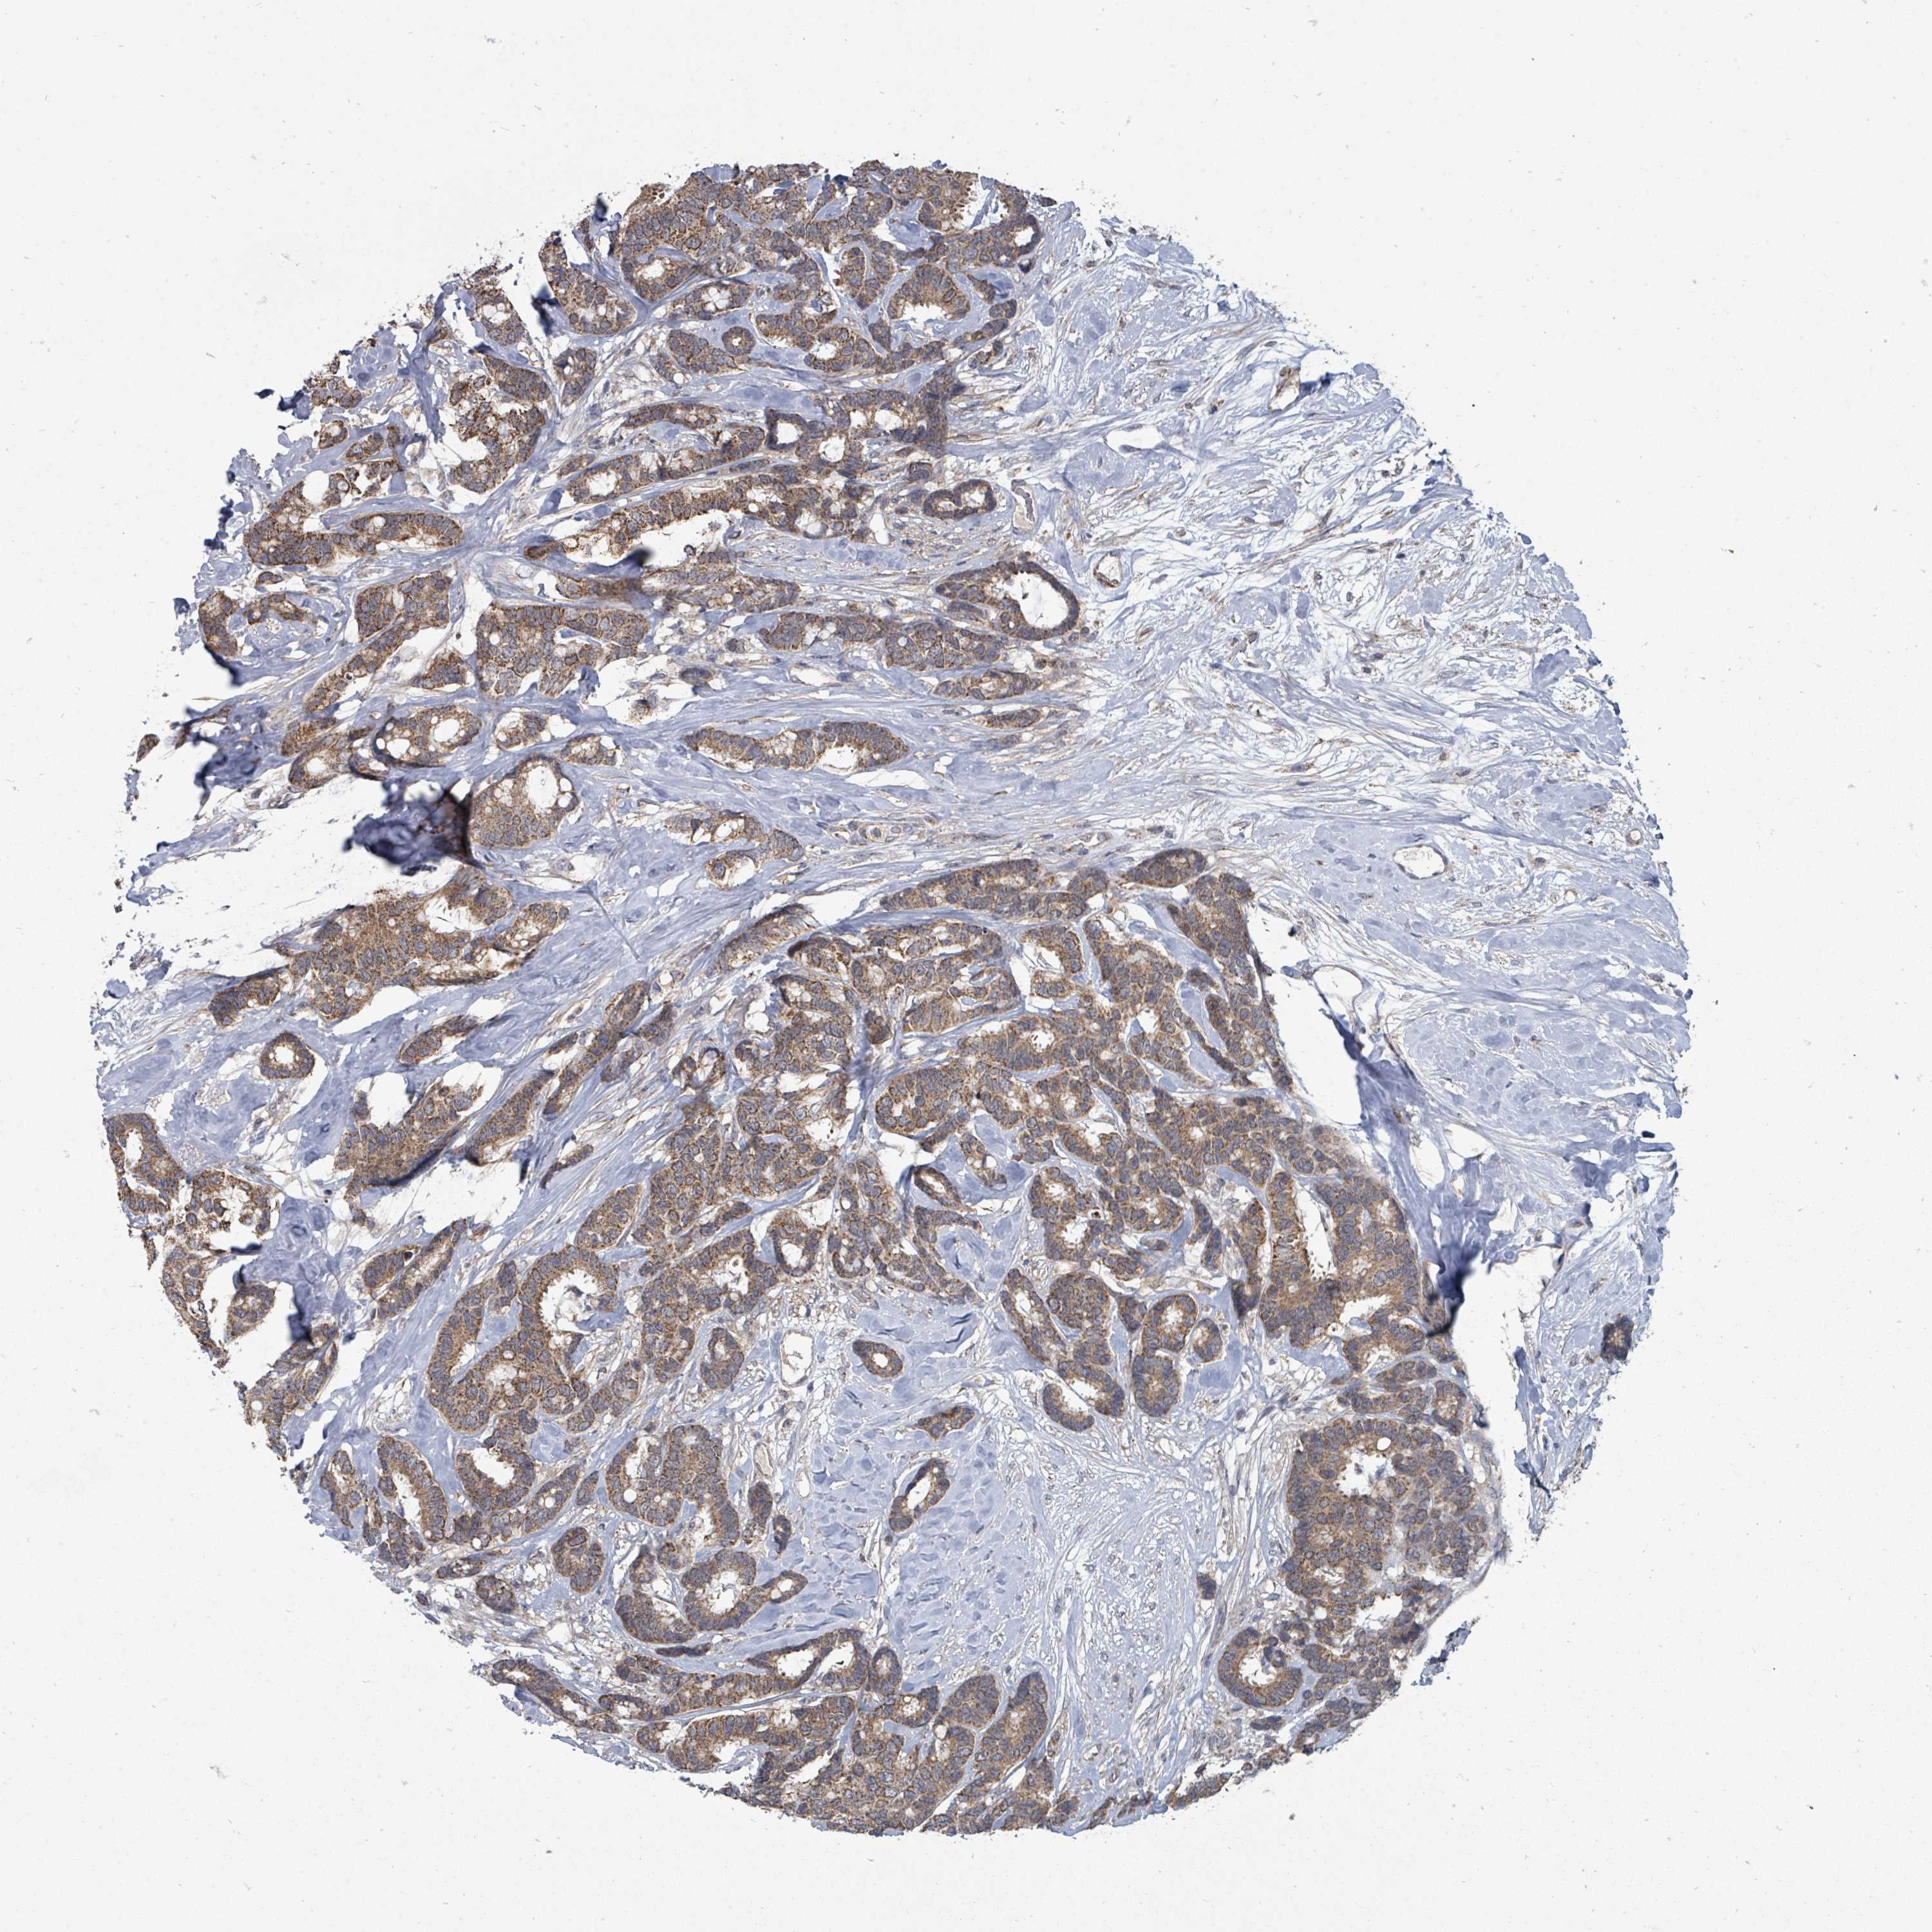

CANCER BREAST CANCER Show tissue menu

BRCA TCGA BRCA VALIDATION PROTEIN EXPRESSION